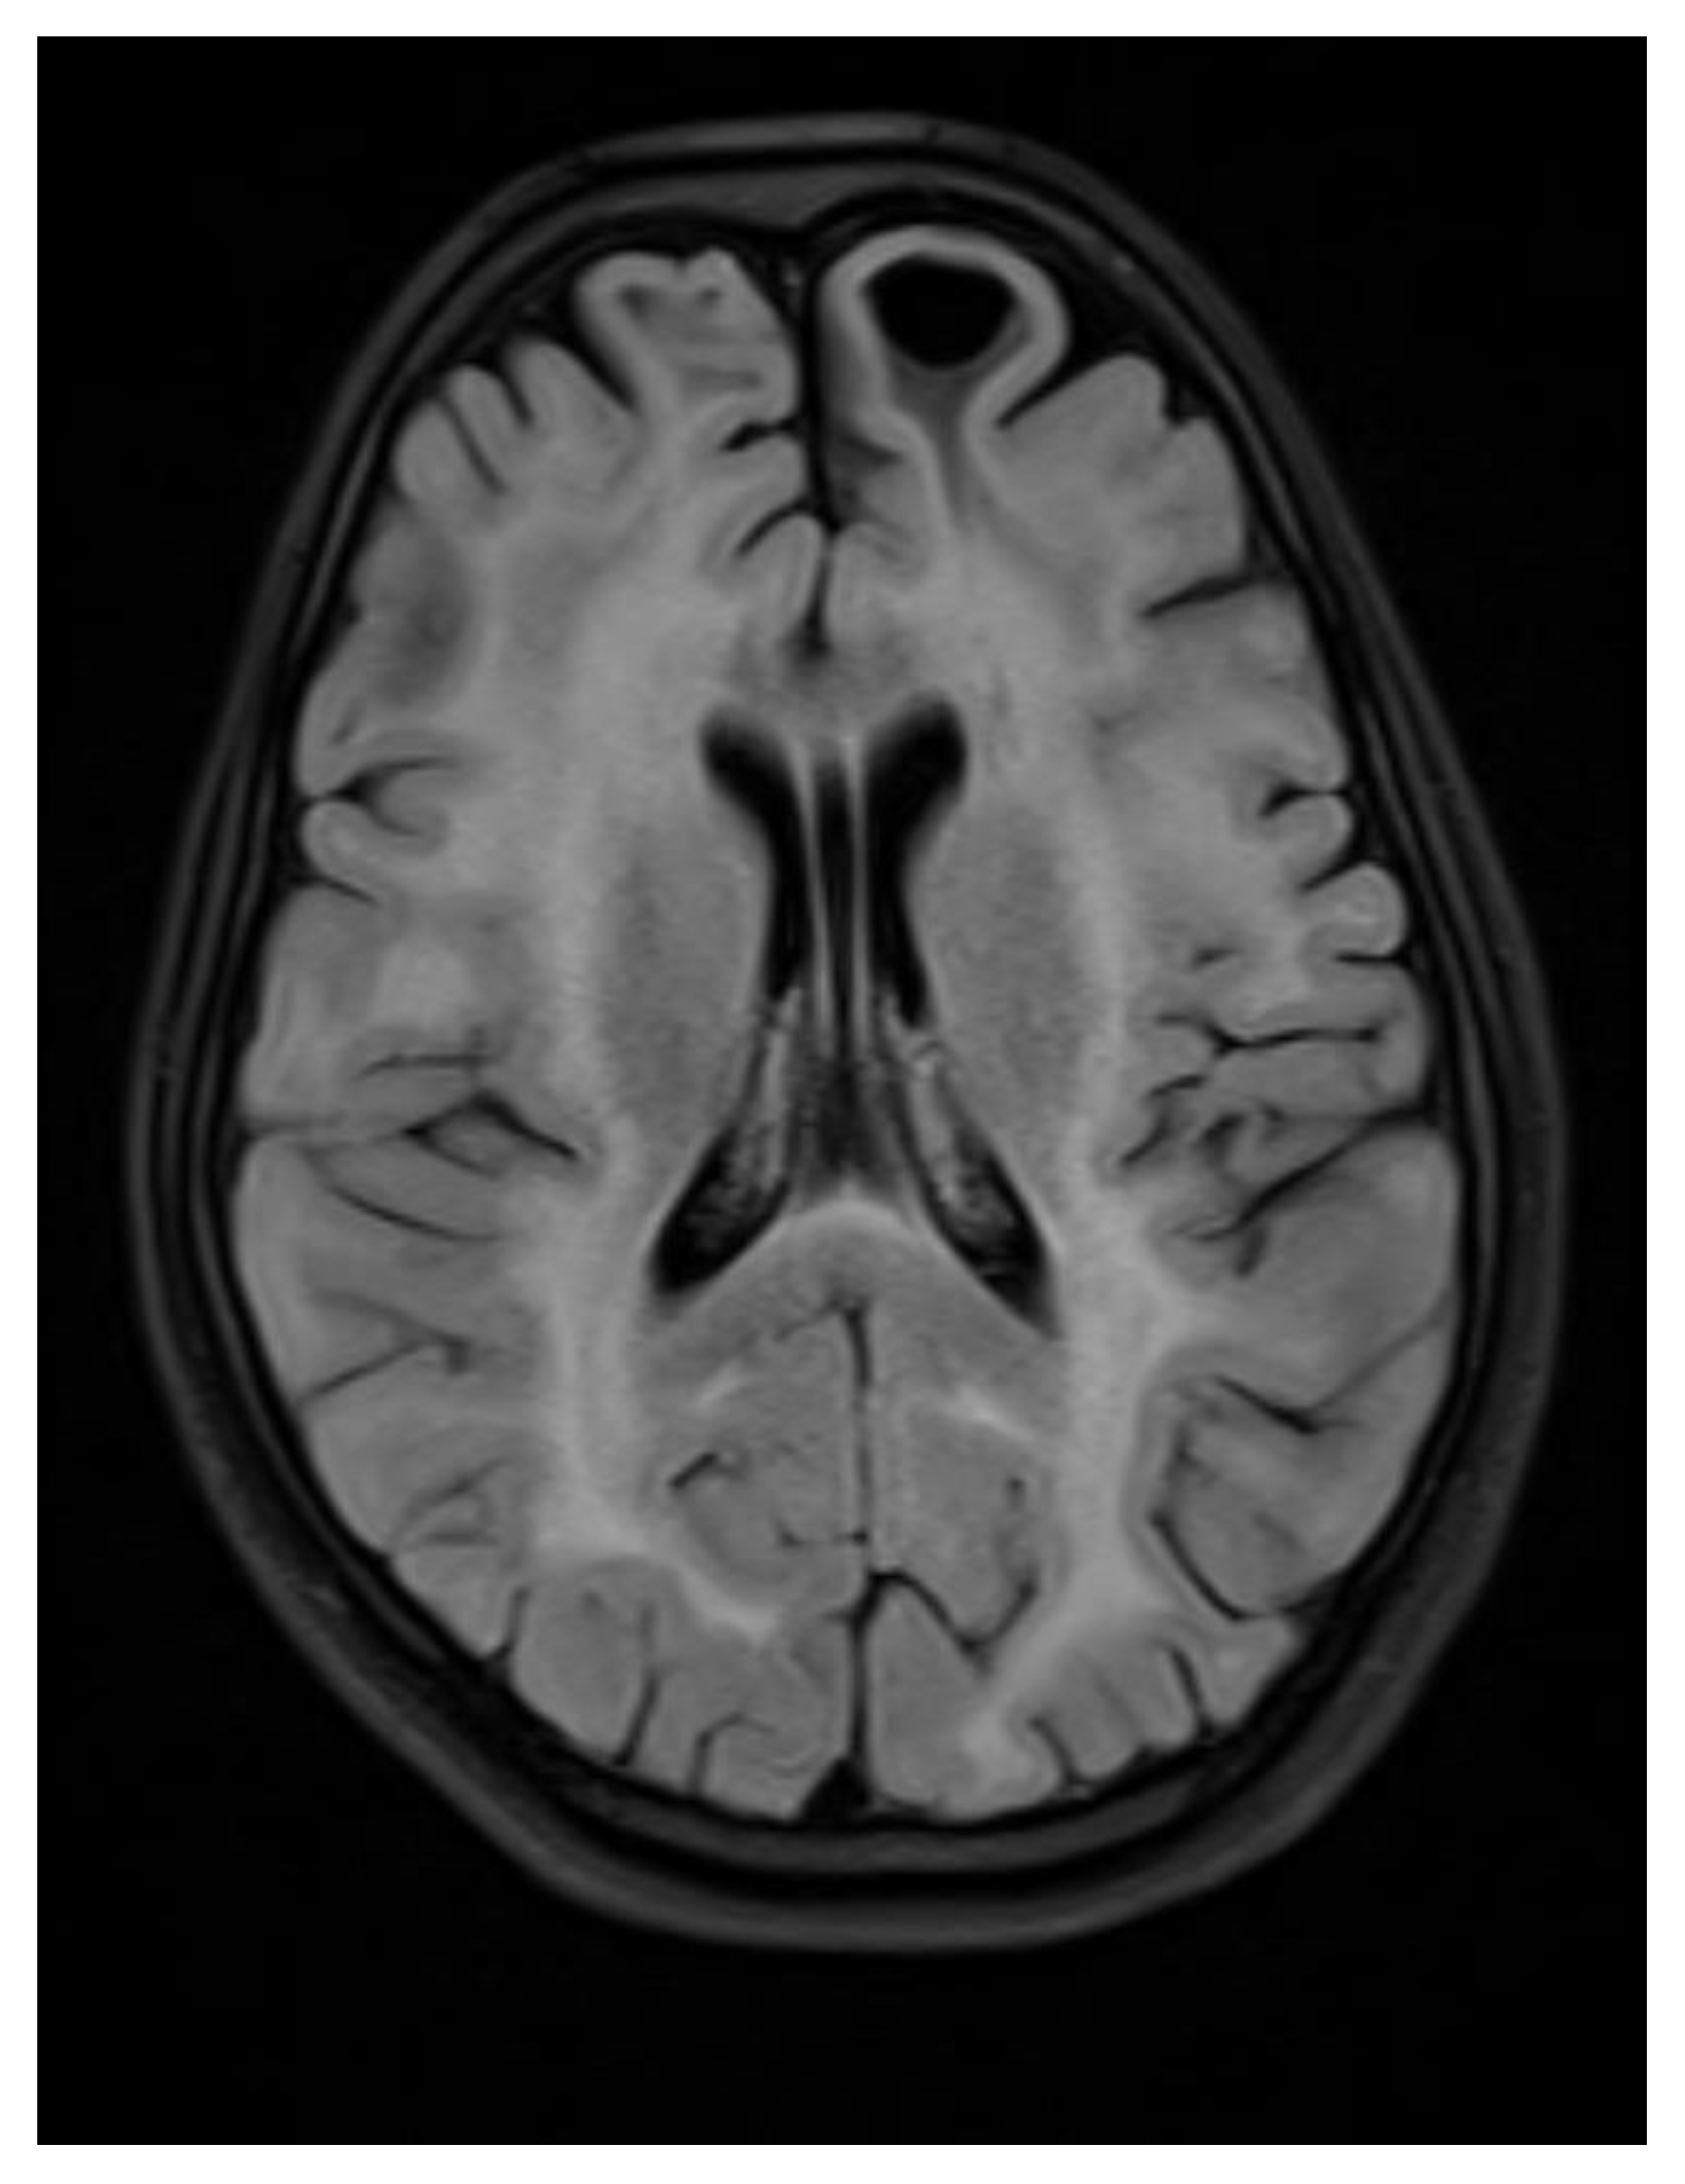

A contrast-enhanced MRI of the brain was performed, bilateral symmetrical diffuse abnormal T2WI/FLAIR hyperintensity involving the subcortical and periventricular deep white matter of bilateral cerebral hemispheres and corpus callosum with areas of diffuse restriction in bilateral centrum semi-ovale restriction, subcortical cysts, and cerebral atrophy were seen with possibility of Megalencephalic leukoencephalopathy with subcortical cysts also known as Van der knap disease. Post-contrast imaging showed normal enhancement, ruling out vascular abnormalities or abnormal enhancement patterns.

Figure 3. Axial flair images showing Bilateral symmetrical white matter hyperintensity with subcortical cyst formation in the left frontal lobe.

Figure 4. Axial T2 WI images showing Bilateral symmetrical white matter hyperintensity with subcortical cyst formation in the left frontal lobe.

Figure 5. Axial T2WI images showing Subcortical and periventricular white matter hyperintensity with subcortical cyst formation in the bilateral anterior temporal lobe.